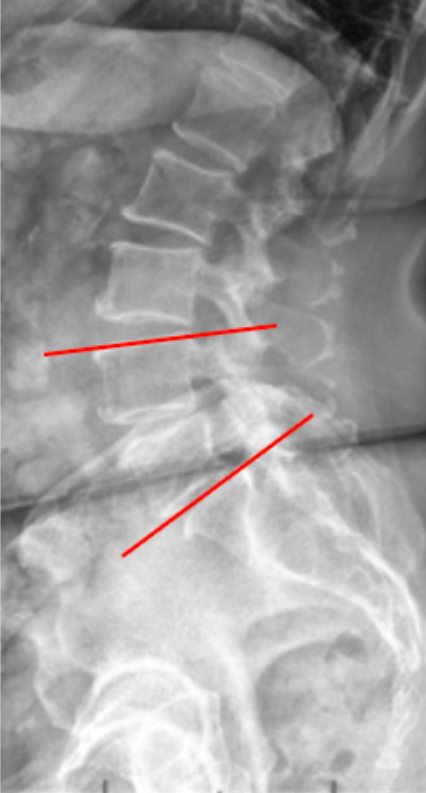

• Identify the superior endplate of the upper vertebra (e.g., L4) and the inferior endplate of the lower vertebra (e.g., S1).

• Draw a straight line along the superior endplate of the upper vertebra.

• Draw another line along the inferior endplate of the lower vertebra.

• Construct perpendiculars from each of these two lines.

• The angle formed at their intersection represents the Segmental Lordosis Angle (°) for that specific segment.

• The angle opens posteriorly, reflecting the normal lumbar lordotic curve.